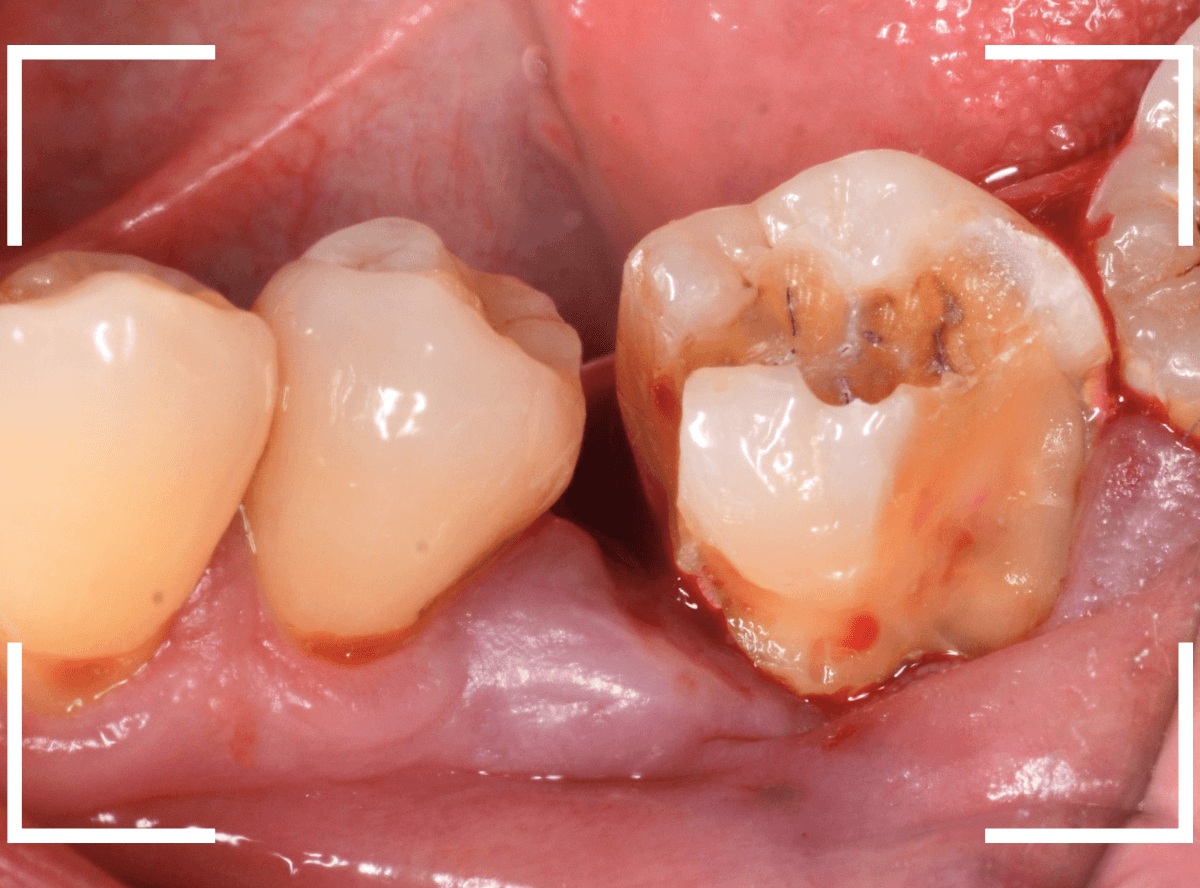

Case.14 CR(コンポジット・レジン)の下の深い虫歯

奥歯で咬んだ時に、痛みを感じるという訴えで来院された患者さんです。

パッと見は特に問題なさそうな状態ですが、大きなレジン治療がしてあり、レジンの奥もボヤっと黒っぽく見えてアヤシイ感じです。

麻酔をして、治療を開始します。

レジンを外すと、中から出血してきました。

これは、歯のスキマに歯肉が入り込んでしまったために起こってしまったものです。

おそらく、随分前から虫歯が進行していたと思われます。

止血しながら、電気メスで歯の中に入り込んだ歯肉を除去します。

虫歯と入り込んだ歯肉でぐちゃぐちゃになっている状態でした。

これでは、痛みが出てもおかしくありません。

慎重に全ての虫歯を除去したところです。

〇部が神経の入り口が見えているところです。

神経を保護する処置をして、しばらく経過観察しますが、痛みが出て神経を除去する必要が出る可能性も高いです。